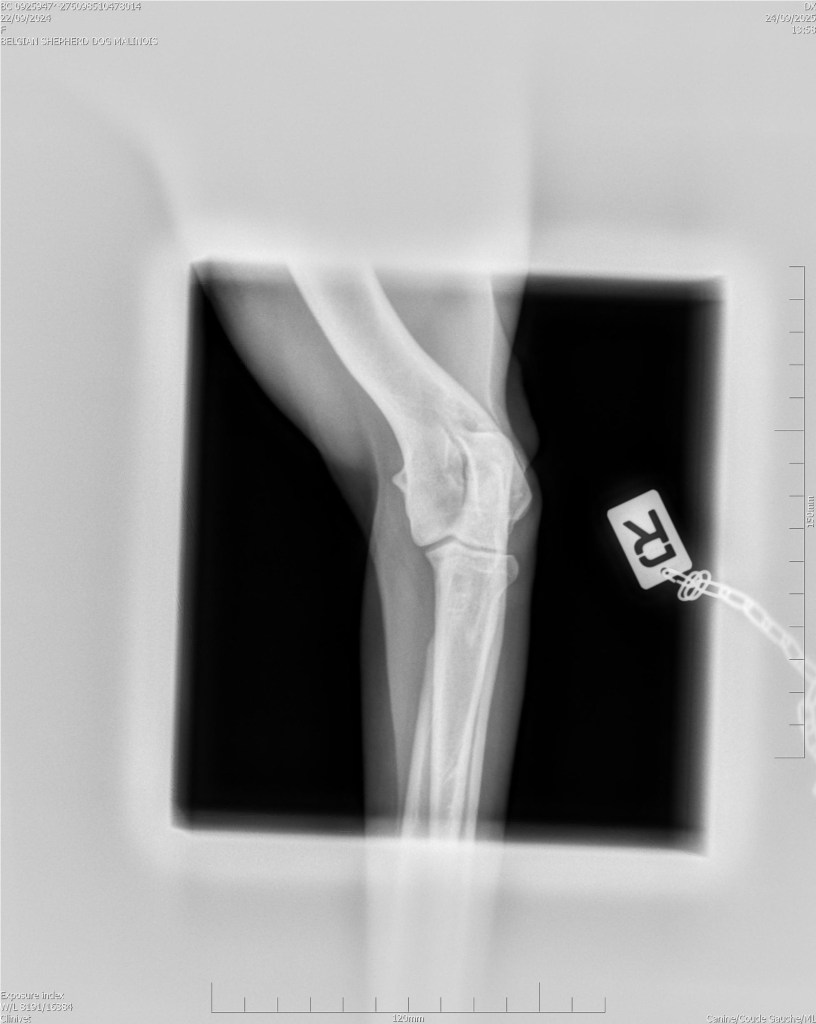

Hips 2/3

Elbows 0/0